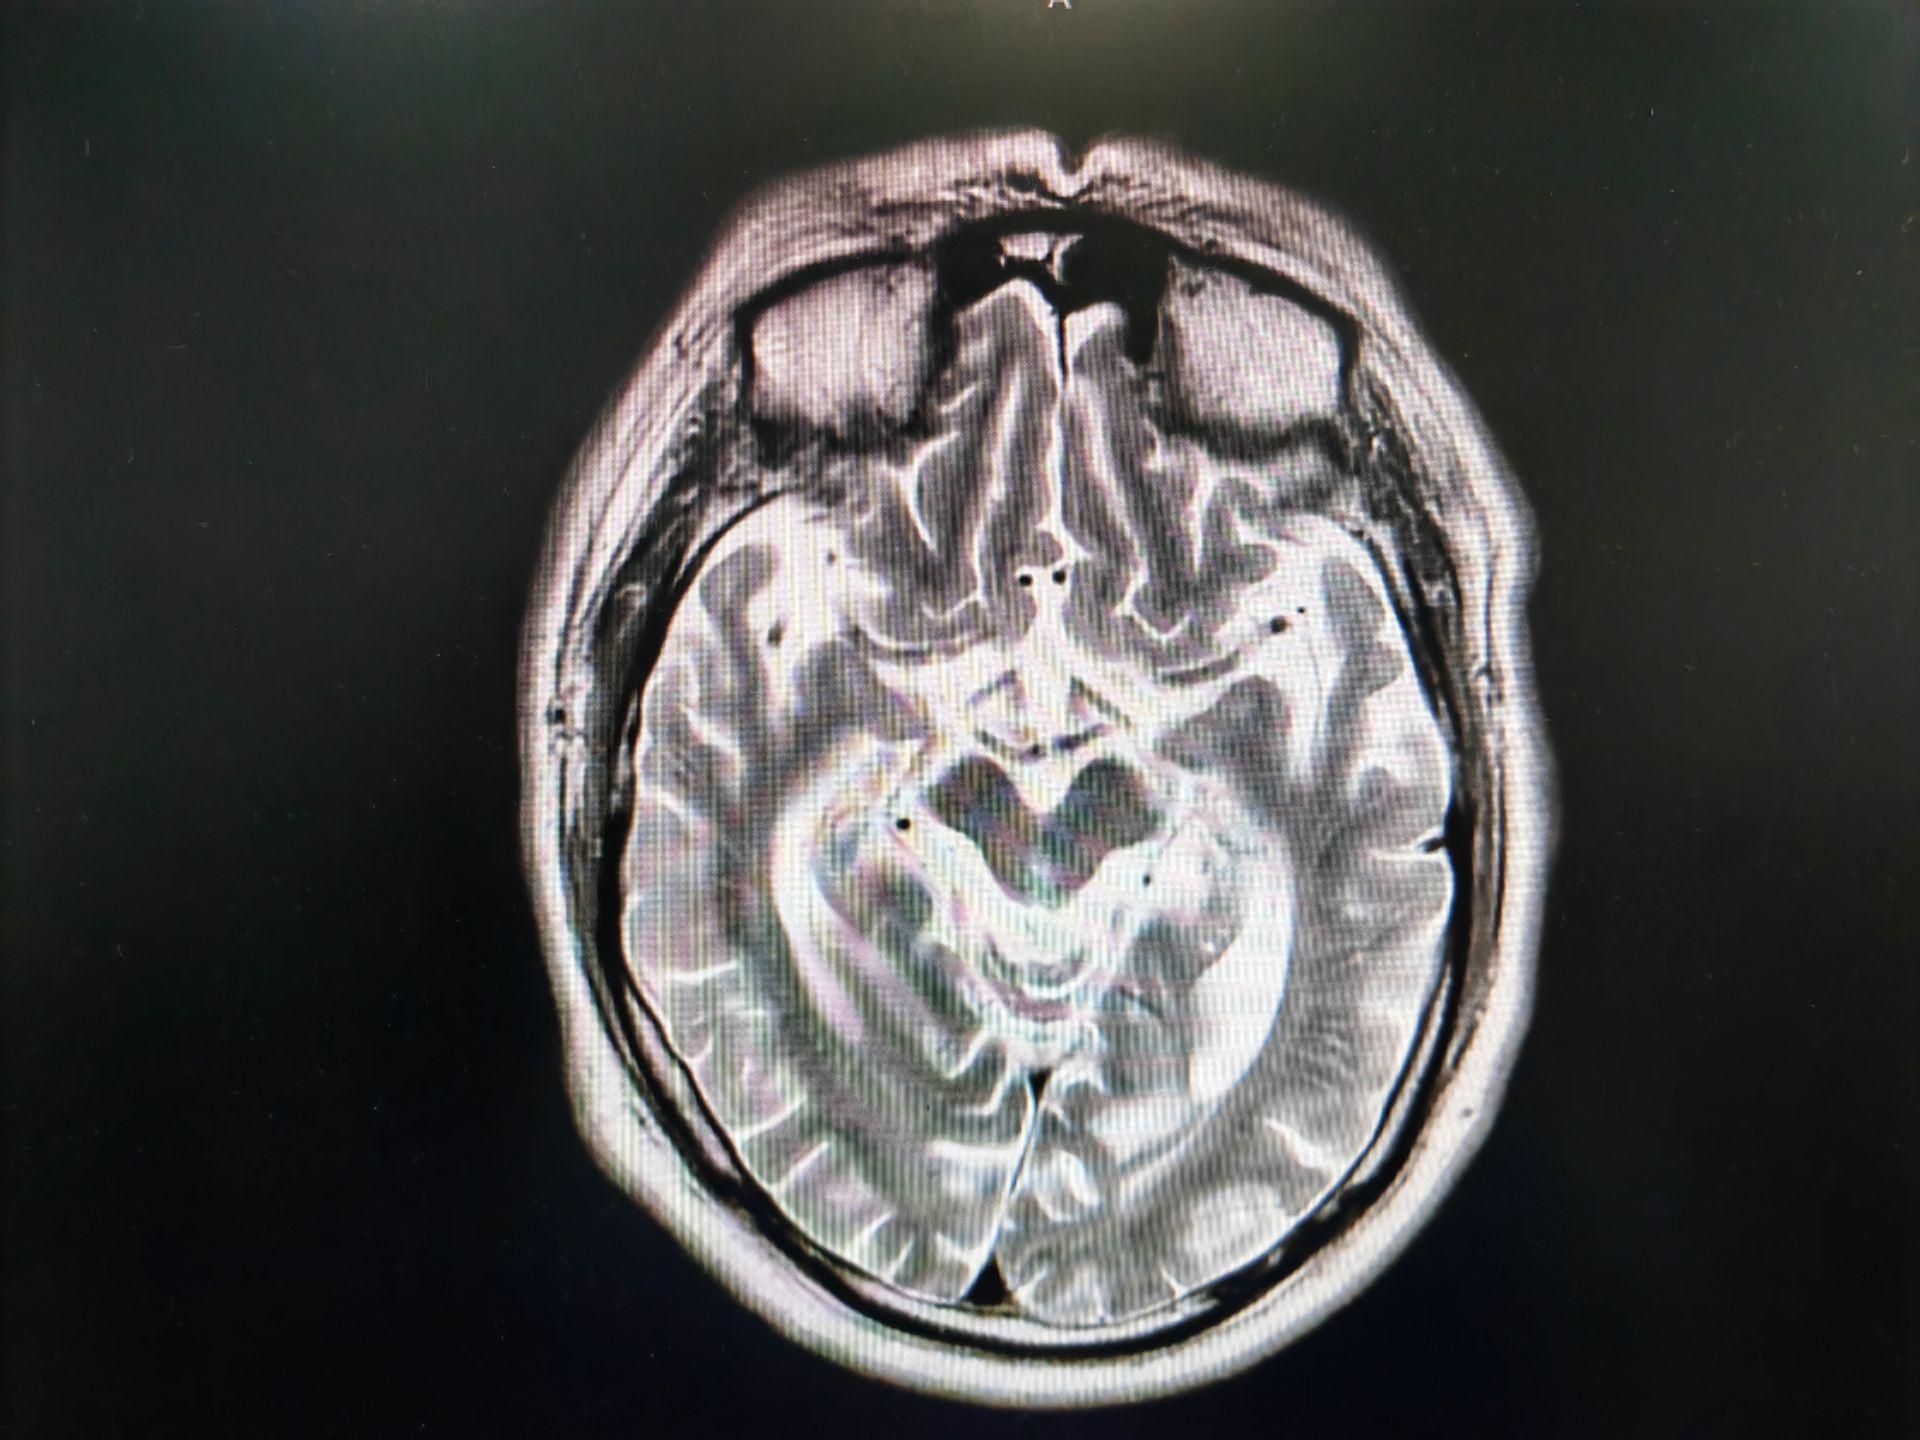

蜂鸟征,米老鼠征,牵牛花征。蜂鸟征 米老鼠征 牵牛花征 进行性核上性麻痹 PSP。PSP 是一种发生于中老年人的中枢神经系统变性疾病,临床表现为轴性强直,垂直性眼球运动障碍, 早期出现反复向后跌倒。但临床诊断为很可能 PSP 患者,经病理诊断证实的阳性预测率约 80%~90%。其临床病理特征为:中脑顶盖和被盖萎缩、黑质色素脱失,第三、四脑室及导水管轻度扩张。